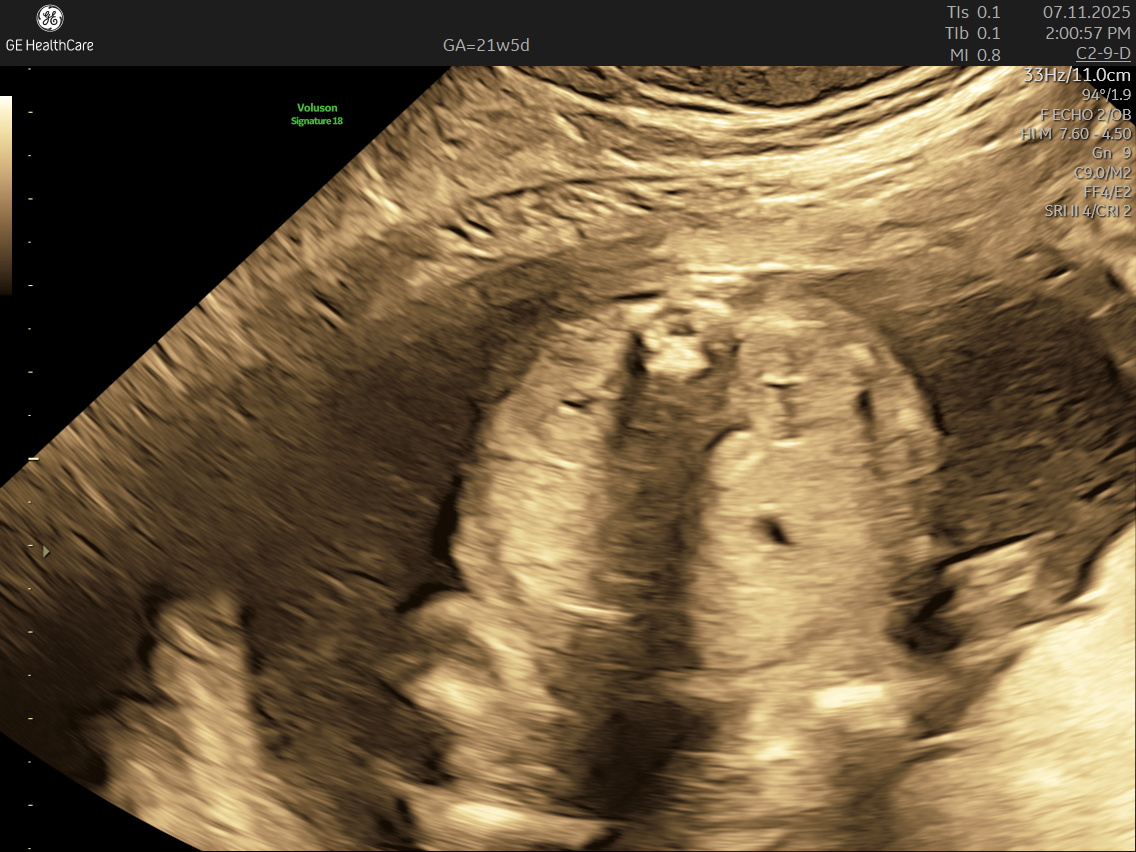

IMAGE GALLERY

If you’re expecting a baby, the Detailed Anatomy Scan —also known as the Fetal Anomaly Scan — is one of the most important checks you’ll have during pregnancy. Usually done between 18 and 22 weeks, this ultrasound is performed by highly trained fetal medicine specialists at NESA Institute of Fetal Medicine. The scan provides a close-up look at your baby’s overall development and helps to make sure everything is progressing as it should.

During this scan, the MFM specialist carries out a detailed examination of your baby’s body, checking their vital organs, spine, head, heart, limbs, and more. The aim is to confirm that your baby’s growth is on track and can identify various structural abnormalities and potential complications early, so that appropriate steps can be taken early.

• Spine and Back: Assesses alignment and formation. A healthy, well-formed spine is a crucial marker of baby’s overall development.